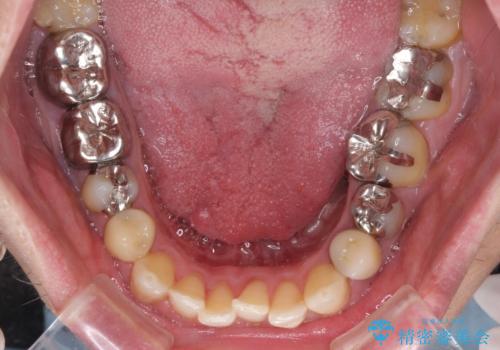

- 飛び出している上顎前歯と、奥歯に多くある銀歯を気にして来院された患者様です。

マウスピースで矯正を行いたい反面、一旦早めに前歯を整えたいというご希望があったため、まずは上顎前歯をワイヤー装置で整え、その後インビザラインにて仕上げていくこととしました。

矯正治療後には、奥歯の銀歯をすべてセラミックにて補綴治療することとしました。

ワイヤー矯正を併用したことで、上顎前歯はあっという間に整いました。

補綴治療にあたり、痛みのある歯に対して根管治療を行うこととしましたが、処置が必要な歯が多かったため、期間を要しました。

補綴治療中に前歯のデコボコが戻ってしまったため、補綴治療後にインビザラインを1セット追加して仕上げました。